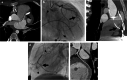

Imaging the coronary arteries of children, with their faster heart rates, small vessel size and common inability to lie still or breath-hold, has been a major challenge. With numerous advances in technology, CT examinations can now be performed quickly, often with children free-breathing and with much lower radiation doses than previously. This has led to increased use in children. Care must be taken with technique and choice of electrocardiogram (ECG)-gating technique to obtain adequate imaging for a diagnosis while keeping radiation dose as low as reasonably achievable (ALARA). In this paper, we discuss techniques and tips for CT imaging of the coronary arteries in children, including use of dual-source- and ultrawide-detector CT scanners.